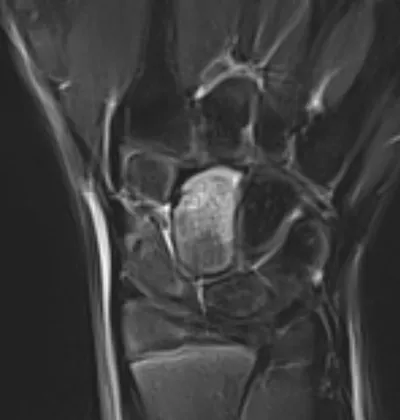

4-Corner carpal fusion of wrist

XRAYHandCarpal+2